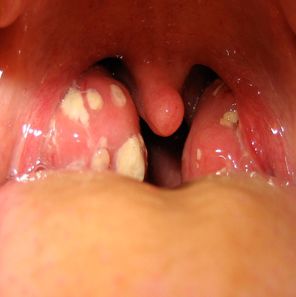

TRATAMIENTO DE FARINGITIS ESTREPTOCOCCICA EVALUACIÓN DE 3 TRATAMIENTOS DIFERENTES.

La faringitis por GABHS es tratada para prevenir la fiebre reumática y para una discreta mejoría de los síntomas. Un tratamiento de 10 dias de amoxicilina (AMX) es lo recomendado habitualmente, en la práctica pedíatrica, dosificandose 2 o 3 veces por día.

La recurrencia de la faringitis estreptocócica en pacientes tratados durante un episodio de referencia, con una dosis diaria de amoxicilina, amoxicilina dos veces al día o cefalexina, se comparó durante el período de 4 meses después del diagnóstico del episodio índice. El criterio de valoración práctica, de la recurrencia de la faringitis estreptocócica sintomática, fue el mismo para los 3 regímenes de antibióticos.